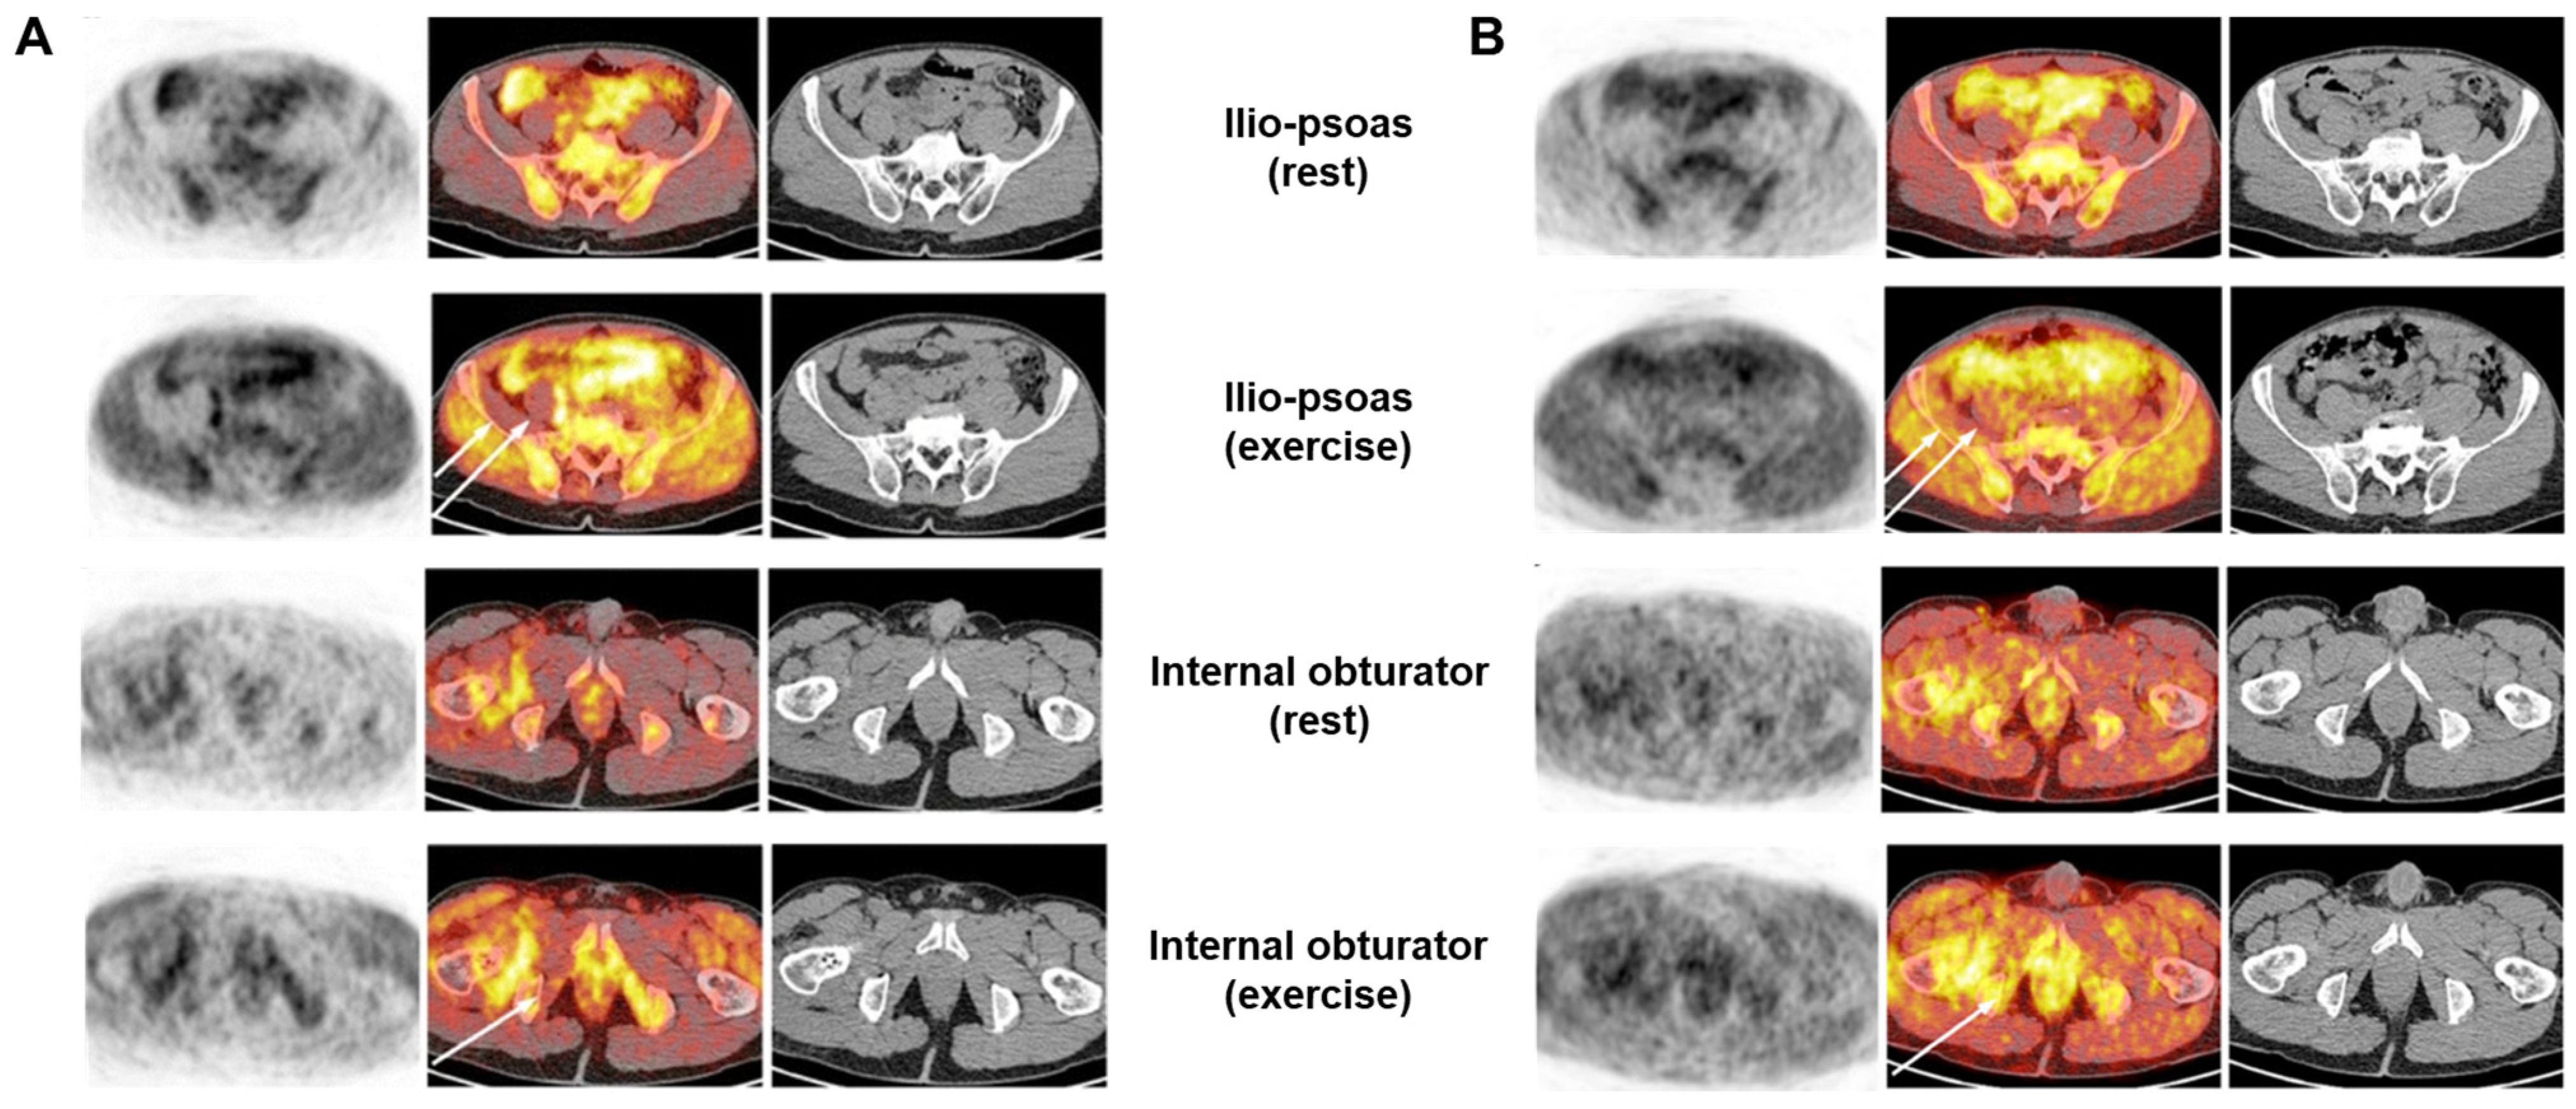

| Healthy volunteers (n = 20) | [18F]FDG was injected 10 min after the start of exercise or after 20 min of rest. Whole-body PET scan was conducted after the exercise or rest periods. | The exercise group exhibited significantly greater uptake than that of the control group in the iliacus muscle and muscles of the anterior part of the thigh. | [30] | |

| Hemiparetic patients (n = 8) | Whole-body [18F]FDG PET scans were conducted after walking. | The [18F]FDG uptake levels in the flounder, foreground, posterior tibia, and obtuse muscles were significantly reduced in the paralyzed muscles of hemiplegic patients compared to non-paralyzed muscles of healthy participants. | [31] | |